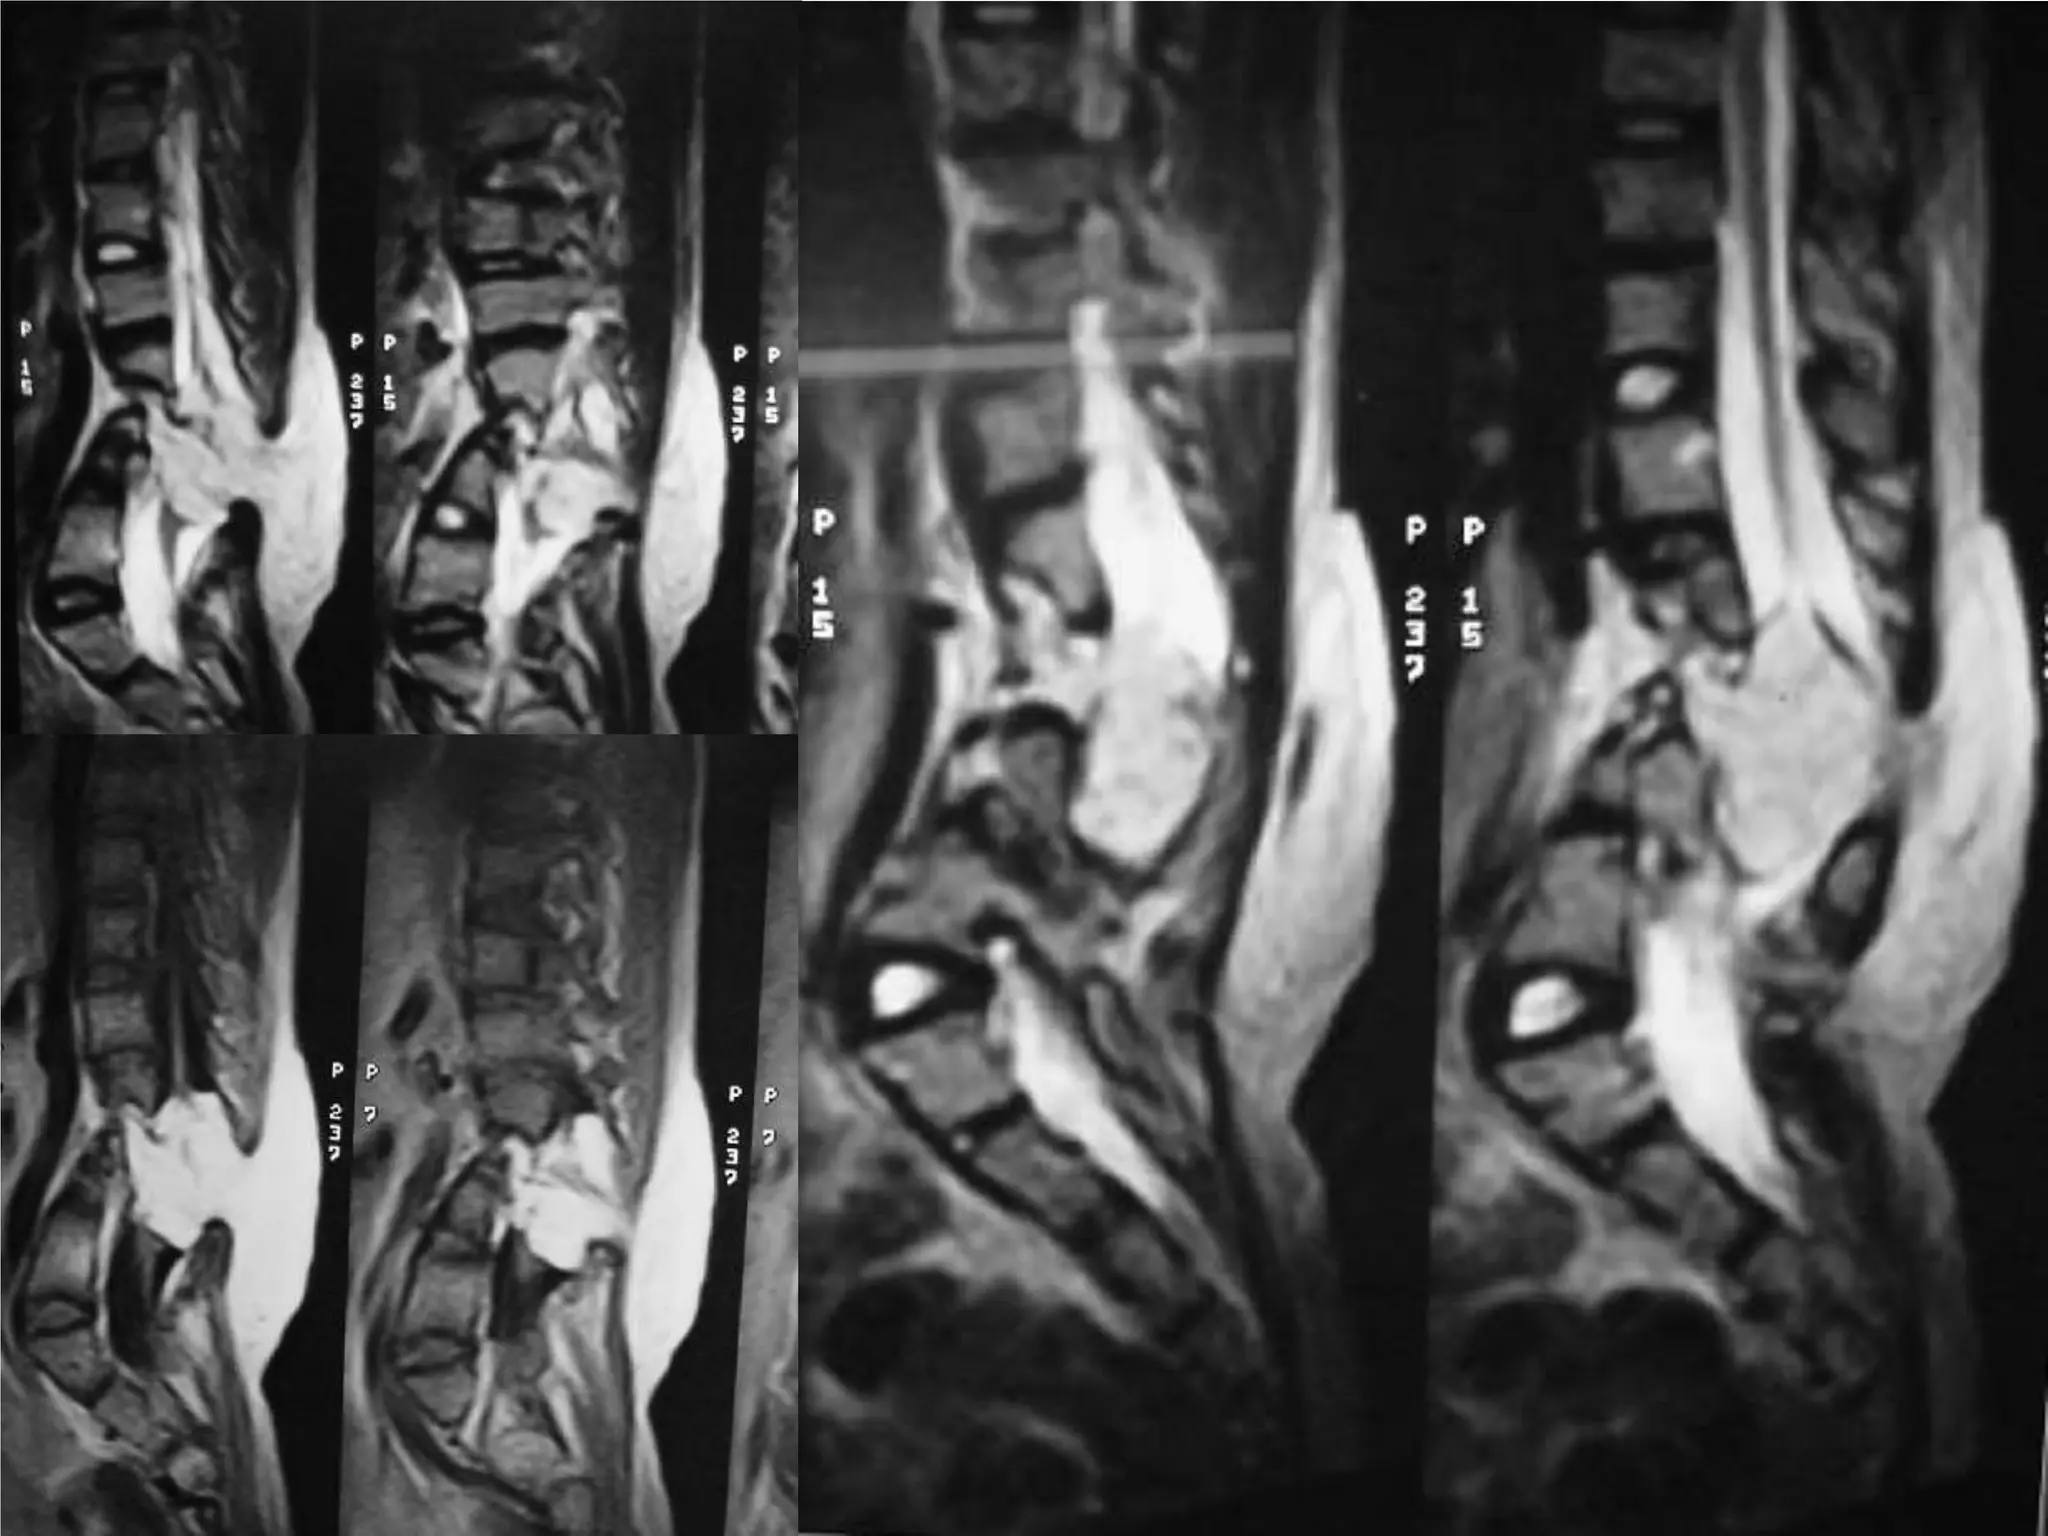

Loose body spinal canal

78 Female, IHD, DMBackache 6 mth.Severe – Bed ridden↑WeaknessCaudaequina – 15 dayDecompressiveLaminectomyEpidural+localLoose body Removed.No improvement